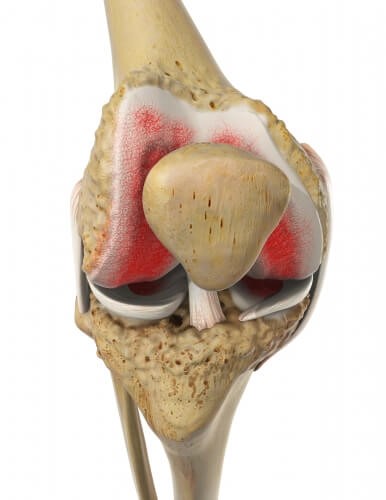

Мы уделили особое внимание такой болезни, как гонартроз, и это не случайно. Действительно, он является основным виновником, который безжалостно разрушает важные анатомические структуры. Замена коленного сустава на протез чаще всего требуется именно при запущенных стадиях гонартроза. Ярко выраженные боли, нестабильность, ограниченная подвижность и отечность окружающих тканей – все это последствия его разрушительного воздействия на костные и хрящевые компоненты.

При данной патологии хрящ, который покрывает суставные поверхности костей, истончается и начинает расслаиваться, теряя свою прочность и эластичность. В результате разрушения хряща суставная щель значительно сужается, что приводит к патологическому трению между большеберцовой и бедренной костями. Это, в свою очередь, вызывает деформацию краев костных поверхностей, которые начинают расплющиваться, и образуются наросты (остеофиты). В конечном итоге возникают трудности со сгибанием и разгибанием конечности, развивается блокировка и нестабильность колена. Исправить такую ситуацию, кроме как с помощью операции по замене поврежденного коленного сустава, уже невозможно.